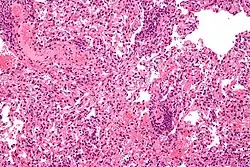

Micrograph showing lung transplant rejection. Lung biopsy. H&E stain.